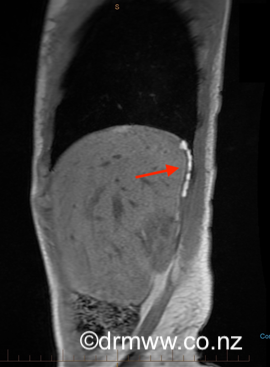

An experienced Endometriosis Specialist usually makes the initial diagnosis by considering the patient’s symptoms along with a thorough history and examination. Because the symptoms can be quite unusual, it’s common for individuals to see various specialists first, such as Cardiothoracic Surgeons, Chest Physicians, or Physiotherapists, before arriving at a diagnosis. Often, many investigations and imaging tests might not show any abnormalities. Chest X-rays and CT scans are commonly done to rule out more common conditions that could explain the symptoms. To confirm the diagnosis more accurately, an MRI performed by an experienced Radiologist is recommended. The best images tend to be captured during a woman’s menstrual period. If the endometriosis lesions are large enough, they can appear as bright white spots (see image 5 & 6).

Image 5 & 6 Posterior diaphragmatic endometriosis seen on MRI as white spots